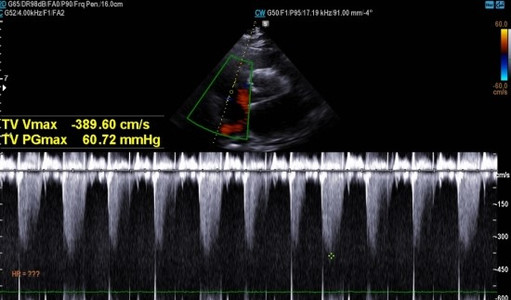

심초음파상 수축기 기능은 정상, 이완기 기능 이상도 경미한 (grade I) 수준

폐동맥 고혈압 소견 관찰됨.